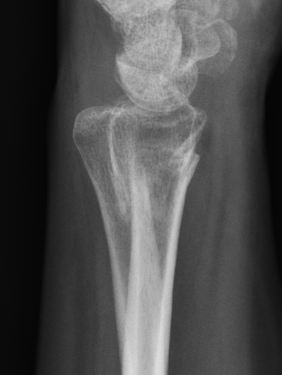

Classification ulna styloid fractures

| Type 1: Tip | Type 2: Base | Type 3: Proximal to styloid |

MRI

Kim et al Arch Orthop Trauma Surg 2023

- MRI of 54 patients with distal radius fracture and ulna styloid fracture

- tip ulna styloid fractures: 88% tears TFCC, 41% DRUJ instability after distal radius ORIF

- base ulna styloid fractures: 89% tears TFCC, 57% DRUJ instability after distal radius ORIF

Ulna styloid fracture with TFCC attached to fragment on MRI with partial tearing